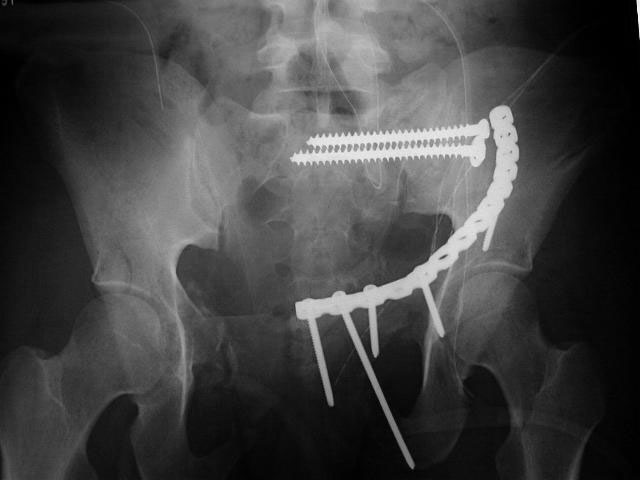

I did as suggested, I performed a 2-stage procedure (posterior sacral osteotomy and anterior take-down of left-sided rami fractures and anterior plate and percutaneous iliosacral screw fixation). It was a difficult and humbling experience. I felt as though the sacral osteotomy was complete and seemed so using intraoperative image views (inlet, outlet and true lateral of the sacrum) however after placing the distractor anteriorly I found that I could not see the sacrum well due to the bulk of the distractor itself. I then replaced it with radiolucent external fixation bars and noted widening of the left anterior SI joint.

Apparently my sacral osteotomy was not complete and the rotational correction (lateral and inferior) was occurring through the SI joint, at least anteriorly. An intraoperative x-ray showed definite improvement of the leg length discrepancy but not complete. I felt that in addition to the rotational correction the left hemipelvis also needed to move inferior as well. Due to the patient's small size, traction on her left leg simply produced pelvic obliquity and I really did not have a way of placing well leg traction which would require a post and at the same time obtain adequate intraoperative image views. Long and the short is I accepted a less than perfect reduction but with leg lengths now with less than 1 cm difference clinically and radiographically and I fused her left SI joint. No post-op nerve deficits. It was definitely a learning experience.

Any and all feed back is appreciated. Postop pics enclosed.

Intraoperative fluoro can be misleading regarding deformity corrections...maybe consider plain films when needed. Notice this lady's external rotation of the left hemipelvis postop and its impact on the acetabular coverage...see the inlet(caudal) view with attention to the ischial spine assymetry.